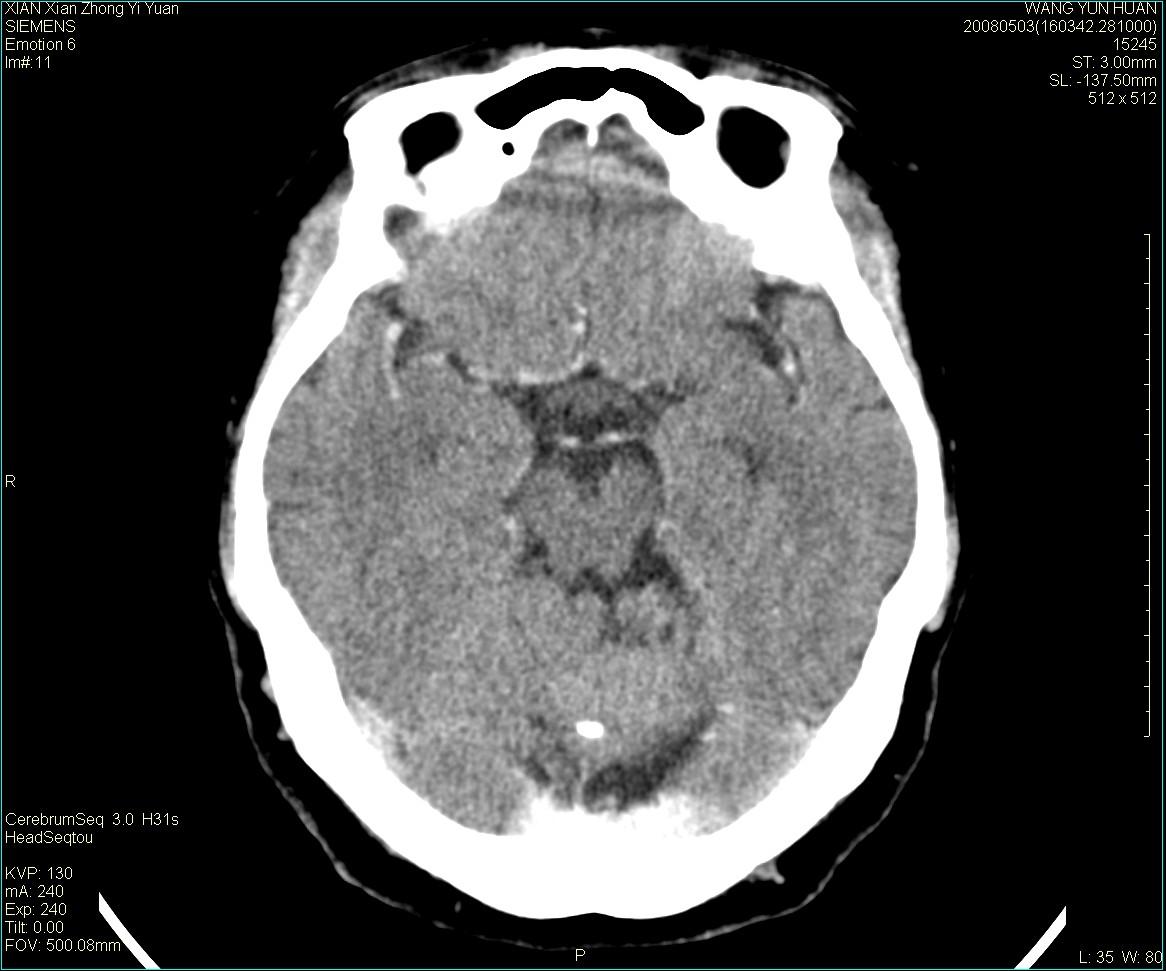

标题: CT13219:(补充强化)请会诊,患者女,60岁,头晕,大家看 [打印本页]

标题: CT13219:(补充强化)请会诊,患者女,60岁,头晕,大家看

病灶显示轻度强化,ct增加4hu左右,大家看是什么肿瘤.

强化后动脉期及延迟2分钟,五分钟图像

小脑蚓部囊型肿块,内有实性结节及钙化点。增强后囊壁及结节轻度强化。

考虑蚓部星形细胞瘤(ⅱ级可能性大)。

小脑蚓部肿块,周围无明显占位效应及水肿带,增强轻度强化,考虑低分级星形细胞瘤。